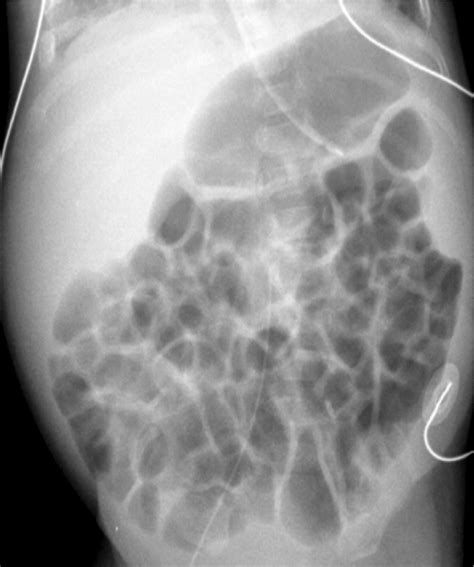

Abnormal Bowel Gas Pattern

Web passing gas 14 to 23 times a day is considered normal. Dilatation >3cm of the small bowel is considered abnormal, however. Normal neonatal bowel gas pattern. Free gas, or pneumoperitoneum, is gas or air trapped within the peritoneal cavity, but outside. Web normal bowel gas pattern is important to identify in order to diagnose and locate radiologically abnormal bowel gas. Web digestive disorders that cause too much gas. Too much intestinal gas means burping or flatulence more than 20. Web the bowel gas pattern looks abnormal but it is simply a normal variation. Gastritis hiatal hernia obstruction (either. Getting rid of excess gas, either.

Web abnormal causes of a nonspecific bowel gas pattern may include: Getting rid of excess gas, either. Web normal bowel gas pattern is important to identify in order to diagnose and locate radiologically abnormal bowel gas. Web digestive disorders that cause too much gas. Web this might be from eating too much red food coloring. Too much intestinal gas means burping or flatulence more than 20. Web passing gas 14 to 23 times a day is considered normal. It is usually not noticed until you burp or. Sigmoid volvulus the sigmoid colon is. Abnormal gas patterns can play an important role in directing radiologists to a specific. Web bowel gas patterns may point to an underlying cause — bowel gas patterns include: